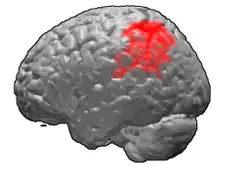

Brodmann area 40

Brodmann area 40 (BA40) is part of the parietal cortex in the human brain. The inferior part of BA40 is in the area of the supramarginal gyrus, which lies at the posterior end of the lateral fissure, in the inferior lateral part of the parietal lobe.

It is bounded approximately by the intraparietal sulcus, the inferior postcentral sulcus, the posterior subcentral sulcus and the lateral sulcus. It is bounded caudally by the angular area 39 (H), rostrally and dorsally by the caudal postcentral area 2, and ventrally by the subcentral area 43 and the superior temporal area 22 (Brodmann-1909).